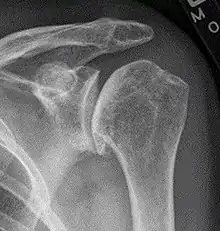

Signs and diagnosis

X-ray of shoulder osteoarthritis.

Arthritis of the shoulder causes pain and loss of motion and use of the shoulder. X-rays of the shoulder show loss of the normal space between the ball and socket. X-ray can provide radiographic staging of shoulder osteoarthritis.